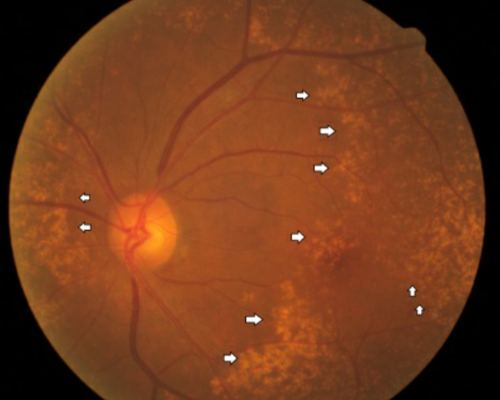

신장, 말초신경, 망막과 전신의 크고 작은 혈관들을 망가트려서 만성 합병증을 일으킵니다. 그 중 당뇨망막병증은 대표적인 당뇨 합병증의 하나로 망막의 모세혈관이 폐쇄되어 조직에 저산소증을 일으키는 미세혈관병증입니다.

망막혈관에서 새어 나온 삼출물과 점상 출혈

혈당관리를 철저히 해도 당뇨병 유발 후 20년이 지나면 대부분의 환자에게서 당뇨망막병증이 나타납니다. 젊은 나이에 당뇨병 진단을 받았다면 당뇨망막병증이 더 빨리 진행될 수 있습니다.